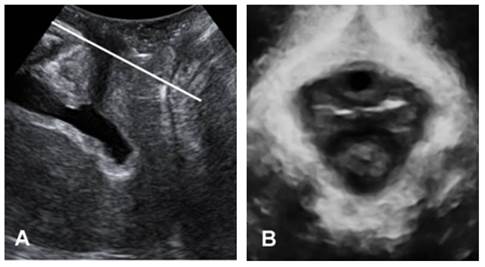

Figure 1 demonstrates the identification of the minimum plane of levator hiatus, in both midsagittal and oblique axial plane[17]. Figure 2 shows the morphological parameters on the minimum plane measured by one experienced investigator: HA (levator hiatus area), AP (anteroposterior diameter of levator hiatus) and LR (transverse diameter of levator hiatus from left to right).

Figure 1

The plane of minimal hiatal dimensions: mid-sagittal plane (A) and axial plane (B).

3D ultrasound performance of levator hiatus in Nullipara group

Levator hiatus was in rhombic shape with compact structure, outlined by puborectalis and pubis. Puborectalis formed a symmetrical and continuous V-shaped sling running from the pelvic sidewall towards the anorectal junction. On the ventral side, puborectalis closely attached to the interior edge of the pubic ramus and surrounded the posterior rectum on the dorsal side. On TUI, the fibers of puborectalis at the site of its insertion were continuous on maximum pelvic floor contraction; avulsion was not detected. On maximum Valsalva, none in Nullipara group was found with pelvic organ prolapse in midsagittal plane. In the axial plane, urethra, vagina and rectum were observed in a line in ventridorsal orientation inside the levator hiatus with clear boundaries.